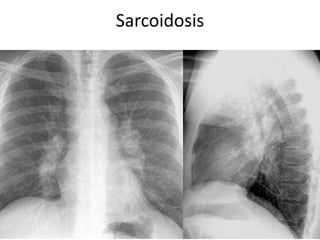

Sarcoidosis